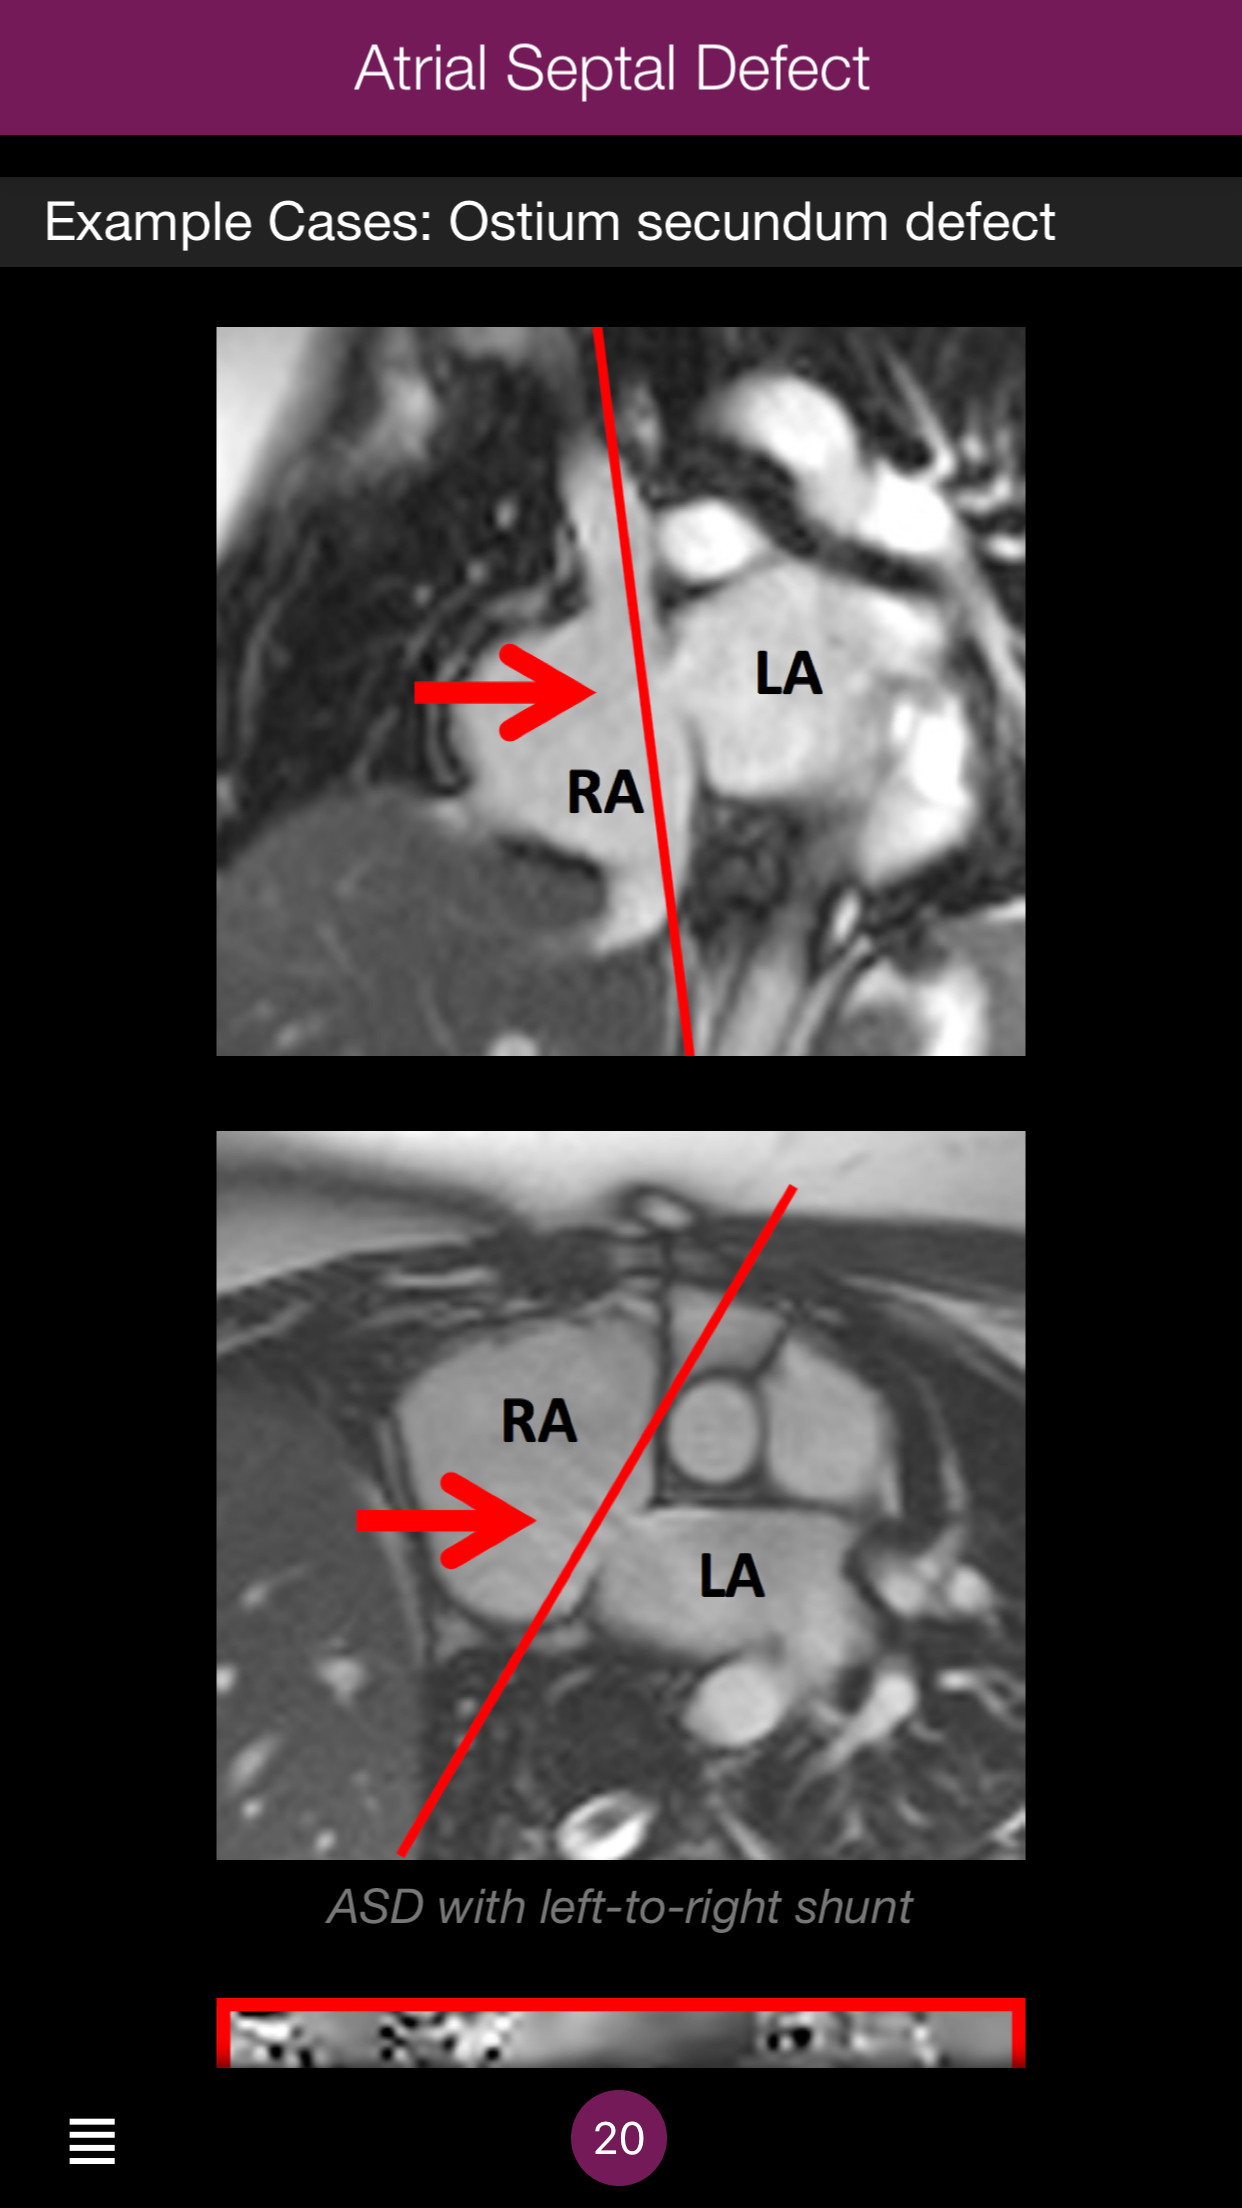

The role of cardiovascular magnetic resonance (CMR) in evaluating congenital heart disease continues to expand. This app aims to provide a day-to-day companion for those new to congenital CMR and for those looking for a quick reference guide in routine practice. The app gives an overview of the most common abnormalities and interventions as well as post-operative complications. It also provides typical scan protocols, key issues and a guide for reporting for each topic.